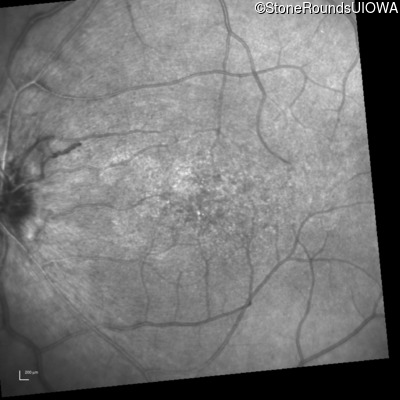

Infrared Fundus Photograph - Right - 20/30 -2

Exemplar